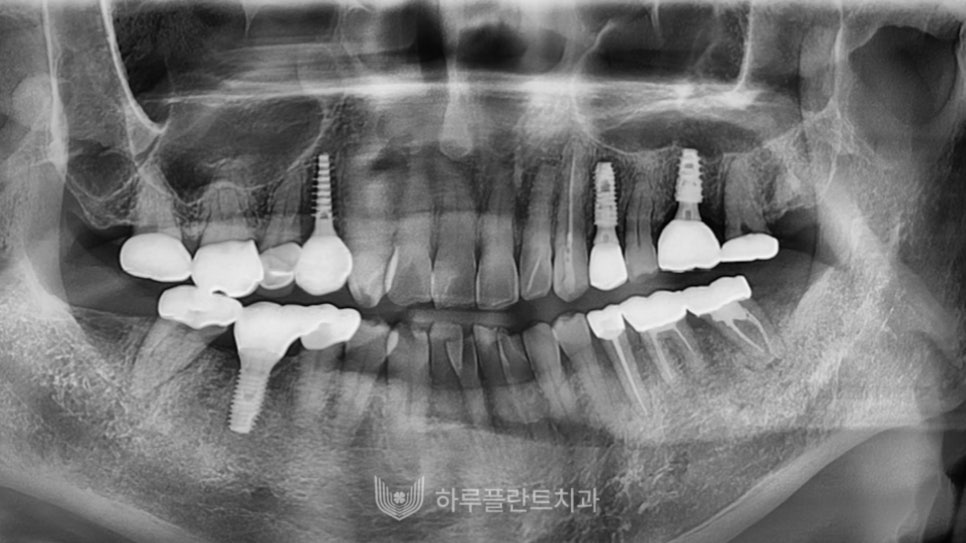

오늘은 당일 임플란트 성공 사례와

과정에 대해 설명드렸는데요,

강남구 당일 임플란트 치과를 찾고 계신다면

치과의 장비 시설과 더불어

치료를 진행하는 의료진의 경험과 실력을

중요하게 체크해 보셔야 합니다.

의료진의 정교한 실력에 따라

수술 결과가 크게 달라질 수 있기 때문에

치과의사의 풍부한 임상경험과 숙련도를

확인해 보는 것이 좋겠습니다.

저희 하루플란트치과에서는

24년 경력의 변성만 대표원장님이

직접 진단과 수술을 진행하고 있으며

사후관리까지 책임지고 도맡아 하고 있습니다.